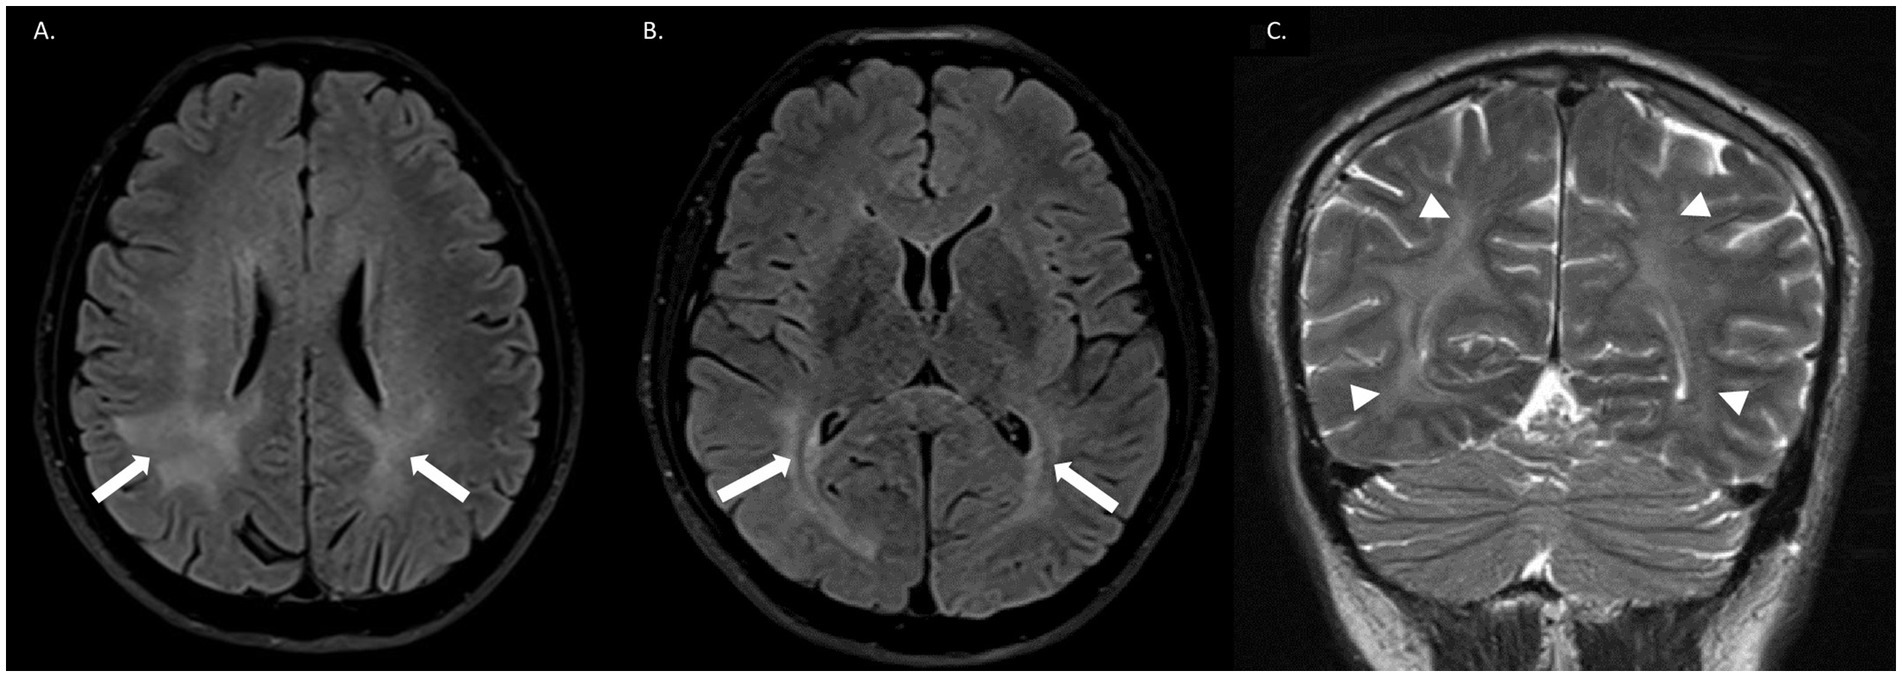

Introduction: Encephalitis in patients with human immunodeficiency virus (HIV) can be caused by opportunistic infections, immune-mediated processes, or direct viral damage. CD8+ encephalitis is a rare condition. We report the first confirmed case in Colombia, diagnosed by cerebrospinal fluid (CSF) flow cytometry. Clinical case: A 50-year-old man with a history of liver cirrhosis and HIV, who had suspended antiretroviral treatment 1 month prior to admission, presented to the emergency department with a 2-day history of disorientation, bradyphrenia, dysarthria, and headache. Neurological examination revealed agitation, disorientation, language, memory, and abstraction difficulties, as well as ataxia and generalized chorea. The patient's CD4 count was 838 cells. Brain magnetic resonance imaging (MRI) showed bilateral asymmetric leukoencephalopathy, and lumbar puncture revealed lymphocytic pleocytosis. After ruling out other differential diagnoses, flow cytometry confirmed the diagnosis of CD8+ encephalitis by identifying 42 cells (59.73% CD8+). The patient's condition improved following the steroid treatment initiation. Discussion: CD8+ T-cell encephalitis is an uncommon immune-mediated disorder in HIV patients, typically occurring when the virus is controlled by antiretroviral therapy. Clinically, it can manifest as global impairment of consciousness, headache and focal symptoms. Diagnosis is typically made via brain biopsy, but imaging and other methods, such as flow cytometry, can be useful. Corticosteroids are the first-line treatment, and prognosis is highly variable. Conclusions: CD8-mediated encephalitis is a rare condition that requires a complex diagnosis. We present a case of an HIV patient who responded well to corticosteroid therapy without the need for a brain biopsy, confirmed by flow cytometry.